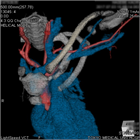

1. 上肢の長時間にわたる同一肢位の継続、反復によって、精神、筋の疲労を背景として発症し、頚椎から肩甲帯に及ぶ筋肉(僧帽筋、胸鎖乳突筋)の疼痛、肩、肩甲骨周囲、腕にかけての痛みやしびれなど頚部、肩、腕、背中を中心としたいわゆる頚肩腕部分の感覚障害が中心となる[1]

1. 痛みやこり感は常在性で、長期間の病期を経過した後に、腕のしびれ、後頭部痛や自律神経症状などが発生するが症状は自覚症状が中心で、神経学的異常所見に乏しい場合に頚肩腕症候群を疑う。